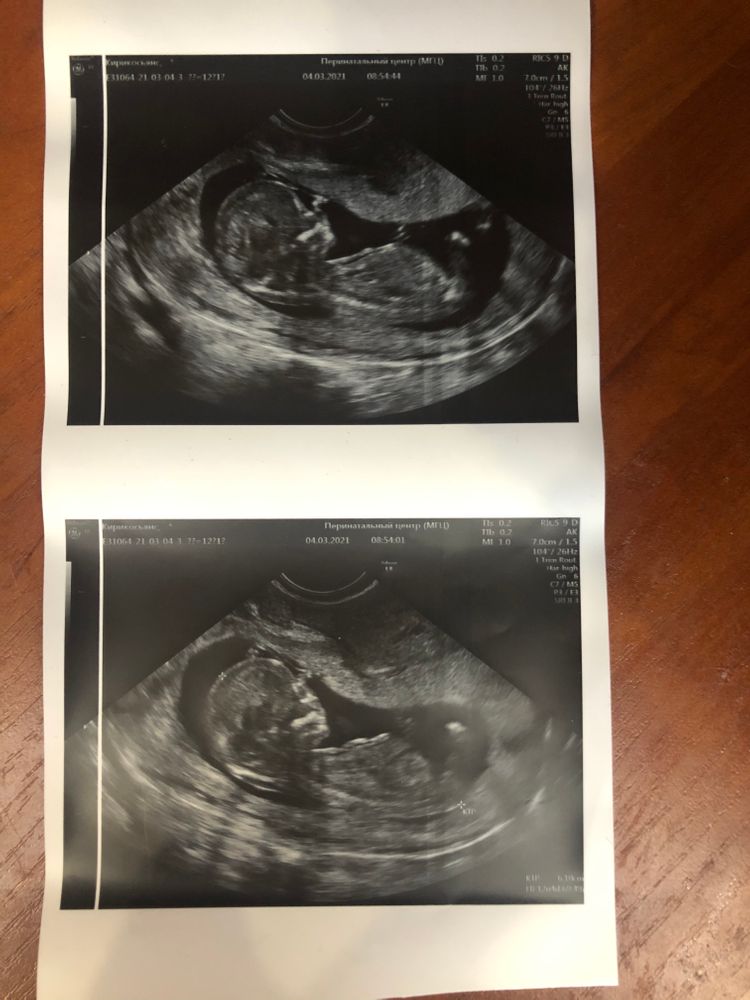

Наши будни, наши неделькиДевочки приветик))видела такие посты и всегда удивлялась как Вы что-то 🙈тут понимаете???????😆😆😆

или у меня совсем неподходящие фото???

Полового бугорка мне видно, но чисто интуитивно по форме головы - мальчик, мне кажется 😁

Милая Мила, да я ж пишу - чисто интуитивно) Никакой "научной" базы нет, просто мне всегда казалось, что на снимках УЗИ мальчики обычно с более выраженным лбом, и головы такие, более "основательные" что ли) А у девочек лбы и головы вцелом более маленькие и аккуратные. Но это все из серии личных впечатлений, не более)

ТигрЮля, у сына как раз был такой весьма выраженный лобик, и голова, как я писала выше, основательная)) Родился, кстати, тоже с большой головой (но это уже в папу, тот тоже родился с большой головой), из-за чего роды были тем ещё приключением. А у дочки вот на всех УЗИ по сравнению с сыном очень аккуратная головка, и лобик более гладкий. У кого из подруг снимки с УЗИ видела - примерно та же картина. Но вы же понимаете, что это чисто моё имхо и кто там на самом деле у вас пока не известно) Бывают и мальчики с аккуратными маленькими лобиками, бывают и девочки с красивыми выпуклыми лбами, это ни разу не признак пола)

Милая Мила, я сына с дочкой на снимках сравнивала, сын по сравнению с дочкой лобастый такой) Хотя вот сейчас я бы не сказала, что лоб у него выраженный. Обычный такой вполне лоб.